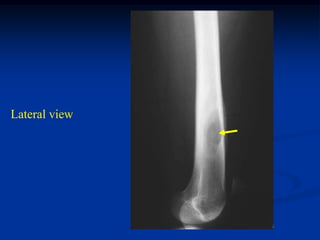

Case #420

3 year female

path fracture

EG femur

Lateral view